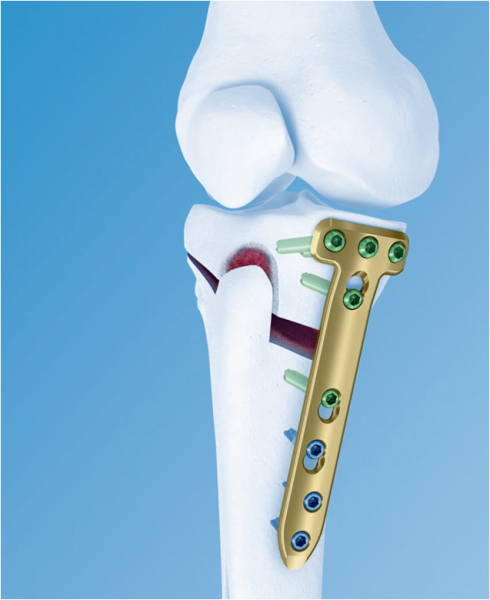

- wykonać zabieg osteotomii piszczeli. Zabieg osteotomii polega na nadaniu nowej osi obciążania kończyny. To skomplikowane sformułowanie kryje w sobie określenie, które zmienia miejsce obciążania kolana. Chronimy w ten sposób miejsce uszkodzone, a kierujemy siły obciążające staw w miejsce zdrowe. Uwalniamy pacjenta od bólu, pozwalając mu kontynuować jego sportowe pasje. W rozmowie z pacjentem lubię posługiwać się porównaniem: kiedy jeździmy samochodem o przednim napędzie, wówczas zmieniamy opony z przedniej osi na tylną, by starczyły na dłużej. Podobnie jest z osteotomią. Zmiana osi obciążania sprawi, że kolano „starczy” na dłużej. Zabieg ten wykonywany jest u osób relatywnie młodych, z ambicjami sportowymi.

Osteotomia piszczeli